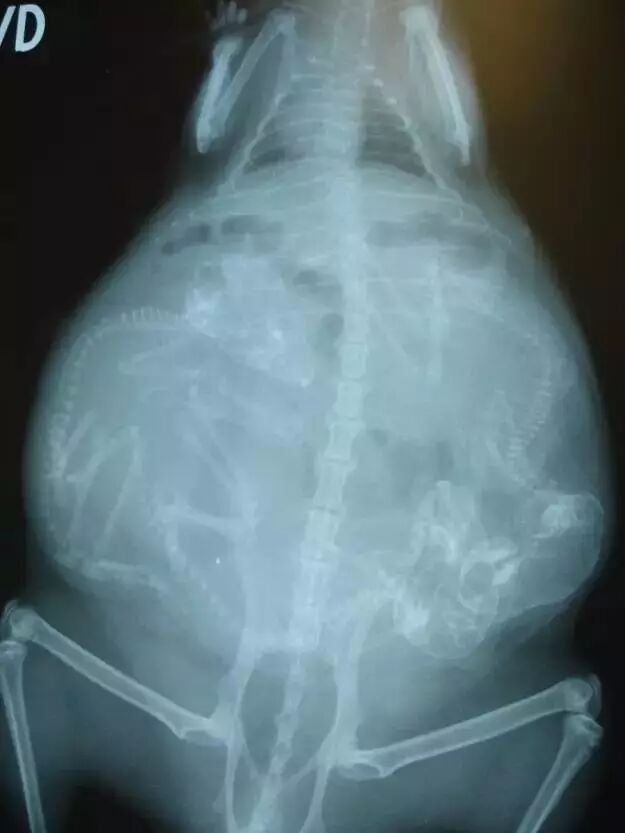

怀孕的猫

还是猫